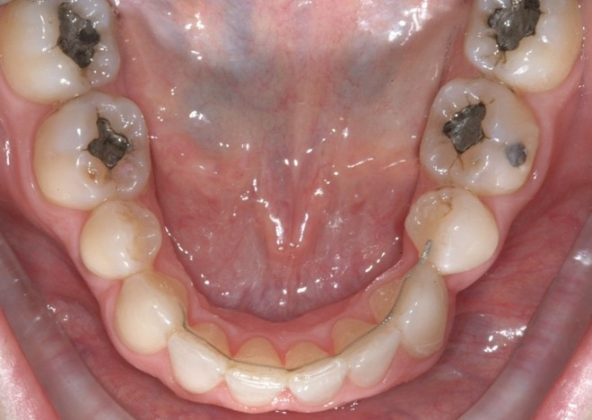

Per formulare corretta diagnosi e piano di cura, lo studio del caso ha previsto la raccolta di documentazione completa standard, ovvero fotografie del viso e intraorali (Figure 1a-e), radiografia panoramica e teleradiografia del cranio in proiezione laterale (Figure 2a-b) per la relativa analisi cefalometrica e modelli di studio.

La valutazione clinica e gli esami effettuati confermano la presenza di agenesia degli incisivi laterali superiori (1.2 e 2.2) e del secondo premolare inferiore destro (4.5).

L’analisi ortodontica e la valutazione parodontale, con particolare riferimento alla posizione della radice del canino superiore destro (1.3), distoinclinata e trasposta alla radice del primo premolare (1.4) come evidente dalla radiografia panoramica e dalle immagini intraorali, ci hanno guidati nella programmazione di un trattamento estrattivo asimmetrico a entrambe le arcate.